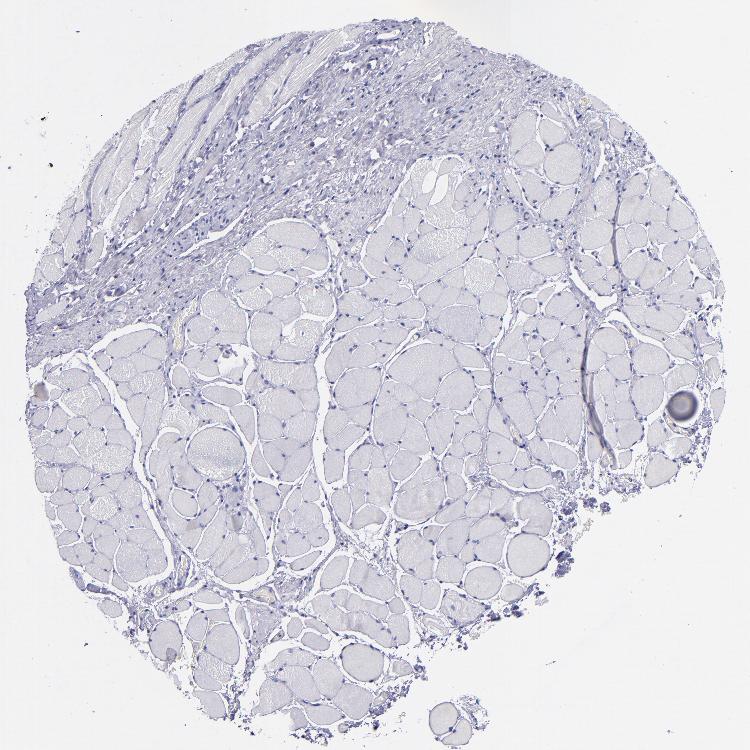

ESOPHAGUS - Antibody stainingi

Antibody staining in the annotated cell types in the current human tissue is reported as not detected, low, medium, or high, based on conventional immunohistochemistry profiling in selected tissues. This score is based on the combination of the staining intensity and fraction of stained cells.

Each image is clickable and will lead to virtual microscopy that enables deeper exploration of all samples and also displays staining intensity scores, fraction scores and subcellular localization as well as patient and tissue information for each sample.

Antibody HPA007863Antibody CAB002226

Squamous epithelial cells Not detectedNot detected